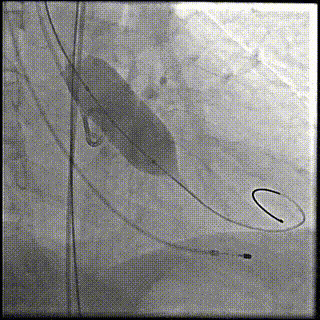

手术影像记录:

主动脉根部造影

22mm球囊预扩

输送器顺利过弓跨瓣

瓣环零位定位释放

第一次释放到工作位

工作位造影位置偏深

完全回收再次定位

第二次释放到工作位,位置理想

瓣膜完全释放

瓣膜完全释放后造影